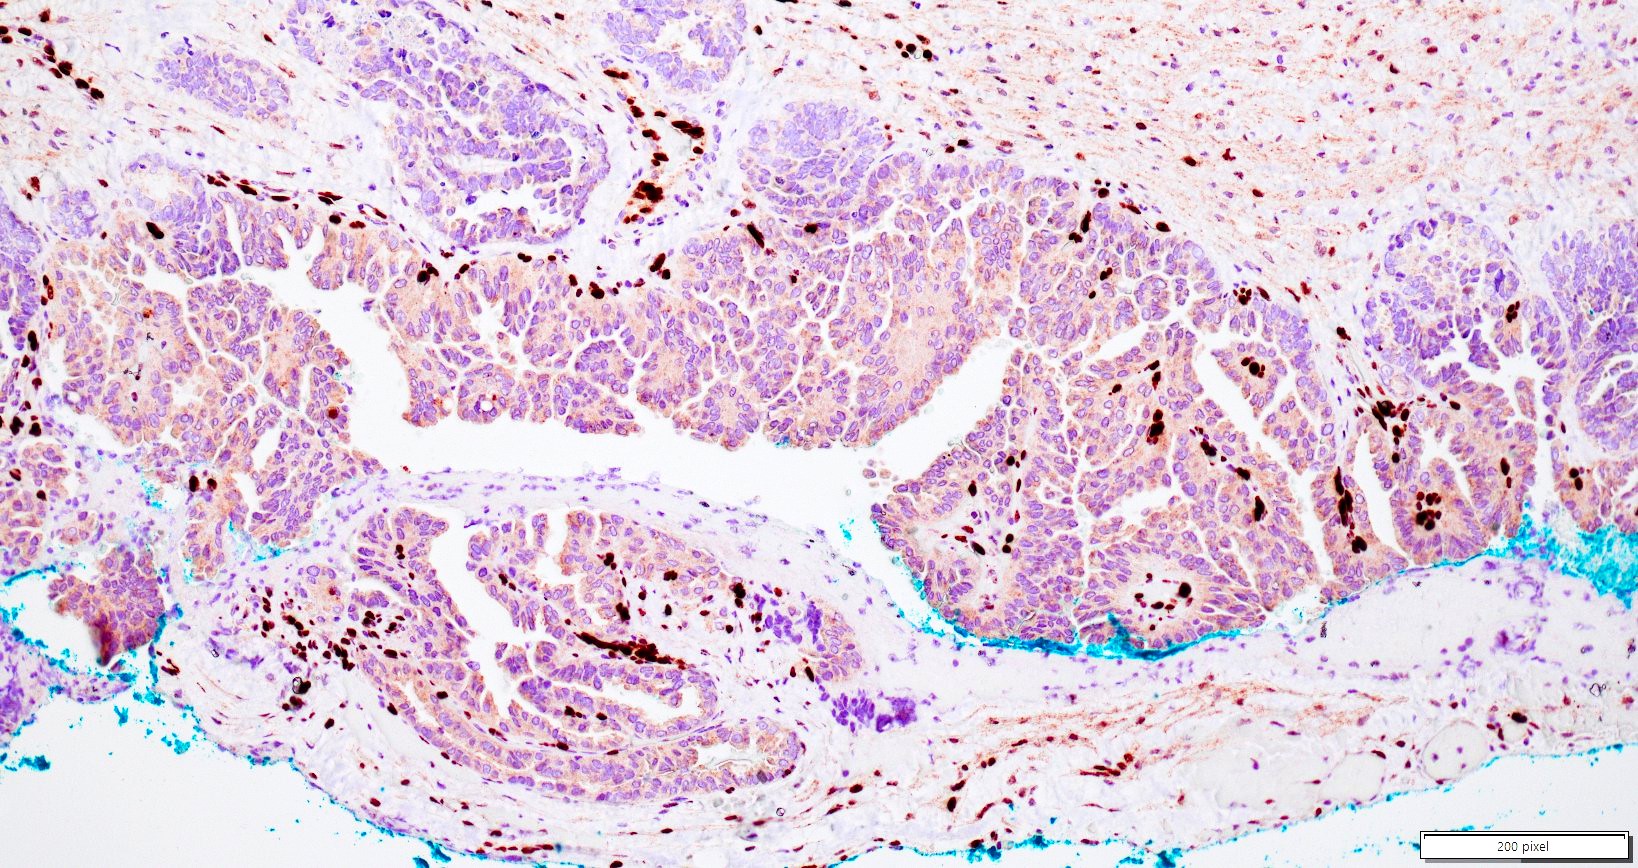

Microscopic (histologic) images

Contributed by Daniel Graham, M.D., Adele Wong, M.B., B.Ch., B.A.O. and Lucy Ma, M.D.

Positive stains

- PAX8: usually diffusely positive

- GATA3 and TTF1: focal or diffuse with inverse staining pattern described in several studies in the most recent WHO classification; cells positive for GATA3 are negative for TTF1 and vice versa (Am J Surg Pathol 2018;42:1596)

- CD10: focal and apical / luminal

- p53 wild type

- MMR proficient

Negative stains

- ER

- PR (more reliable negative marker than ER)

- Calretinin (usually negative may be focally positive)